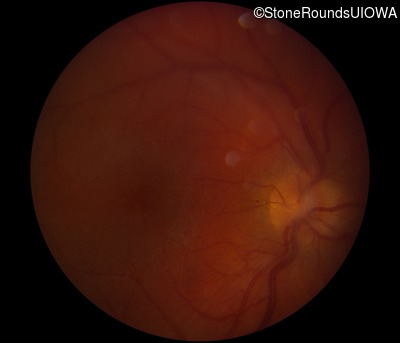

Fundus Photography - Right - 20/300 sc

Exemplar